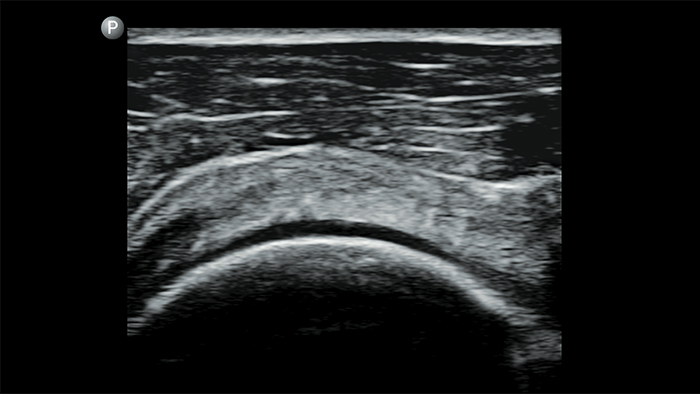

Echografieonderzoeken kunnen helpen om huidabcessen te identificeren en succesvol te behandelen.

Lumify kan helpen de subtiele details van een beeld zichtbaar te maken en afwijkende weefselstructuren bloot te leggen vanuit verschillende hoeken. Hierdoor kunt u met vertrouwen realtime beslissingen nemen, van diagnose tot herstel.

POC-echografie voor zacht weefsel